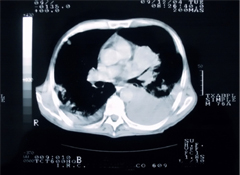

Researchers have been looking at several screening approaches, with one of the most promising being low-dose spiral CT scans. These scans can produce detailed pictures of cross-sections of your lungs. Studies show that CT scans can detect more early-stage lung cancers than chest X-rays. But it has been unclear whether this might prevent many deaths. That's where the new study comes in.